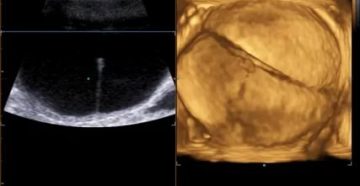

Многокамерная киста яичника: лечение, операция, больших размеров Многокамерная киста яичника – один из самых опасных…

Киста с пристеночным солидным компонентом — опухолевый процесс, формирующийся вследствие скопления фолликулярной жидкости в кистозном…